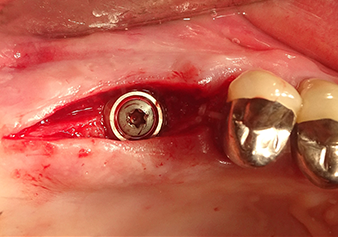

Dopo un controllo intermedio (Fig. 4) è stata eseguita un'ulteriore fase di preparazione (Fig. 5). Lo strumento idraulico Z35P è stato utilizzato in un secondo momento per sollevare la membrana sino alla posizione desiderata (Fig. 6 e 7). In seguito alla suddetta operazione, si è proceduto ad una ulteriore preparazione piezochirurgica della sede dell'impianto conclusasi con l'applicazione della fresa e della fresa a spallamento sul diametro dell'impianto di 4,8 mm. Il materiale di rinforzo (dimensione delle particelle di ca. 0,8 - 1,6 mm) è stato introdotto sotto la membrana di Schneider prima che venisse inserito l'impianto (Fig. 8).

Situazione dopo aver inserito l'impianto

Fig.9: situazione dopo aver inserito l'impianto (lunghezza: 10 mm, piattaforma protesica: 6,5 mm) immediatamente prima della sutura.